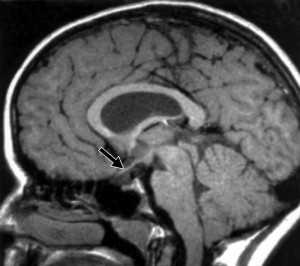

МРТ. Т1-зависимая сагиттальная томограмма. Септооптическая дисплазия. Гипоплазия воронки.

Септо - оптическая дисплазия состоит из триады признаков, выявляемых при МРТ: отсутствия прозрачной перегородки, гипоплазии зрительных нервов и гипоплазии воронки. Отсутствие прозрачной перегородки приводит к деформации желудочков. Передние рога боковых желудочков вздуты и закруглены. Синдром нередко сочетается с атрофией или агенезией мозолистого тела. В диагностике очень важно исследовать состояние зрительных нервов.